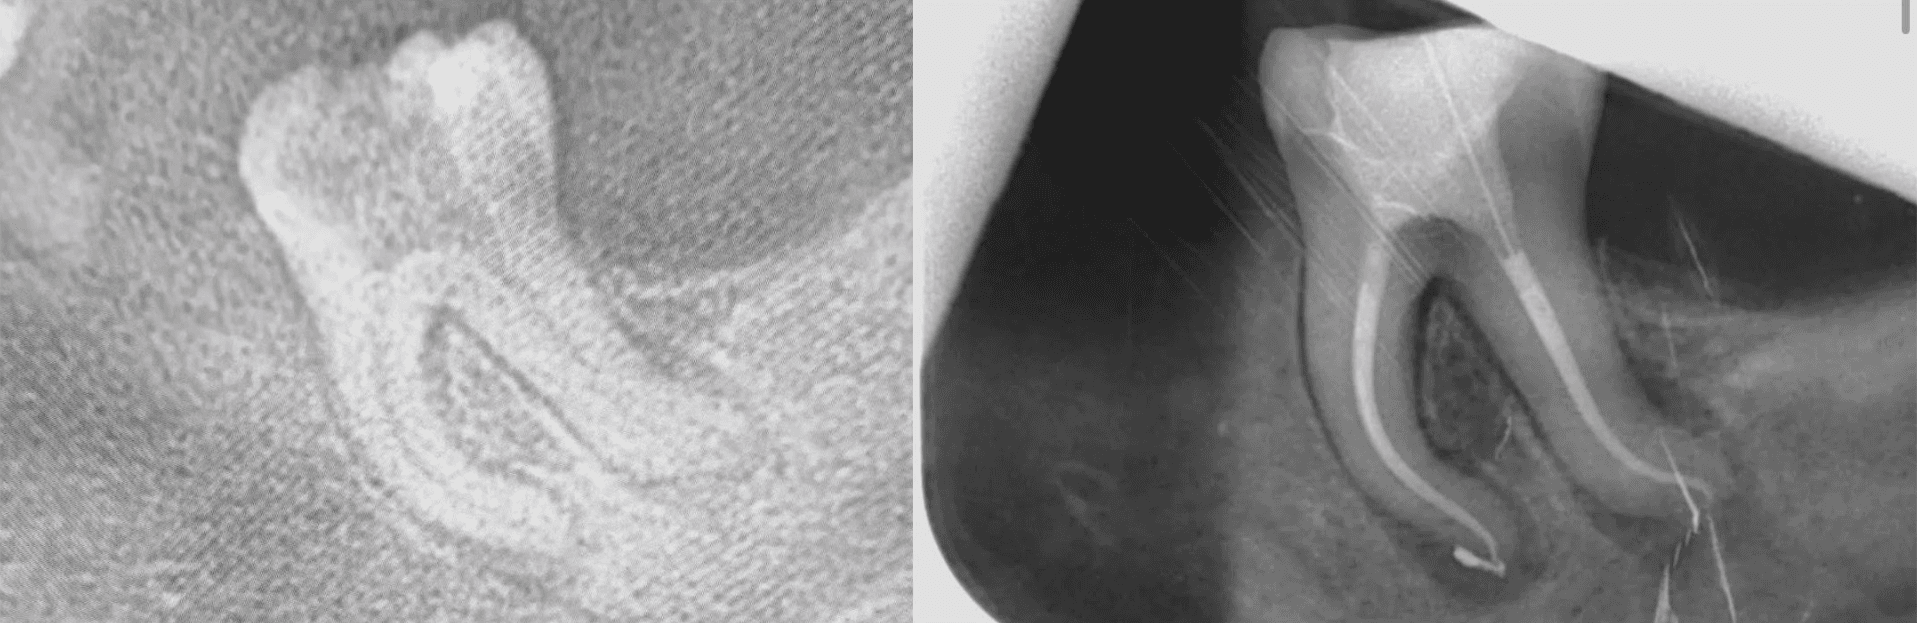

Începem cu o diagnosticare detaliată—imagistică de înaltă rezoluție, CBCT și teste de vitalitate. Acestea ne permit să confirmăm indicația pentru tratamentul de canal și să evaluăm starea dintelui, atât structural, cât și în relație cu alte tratamente din plan.